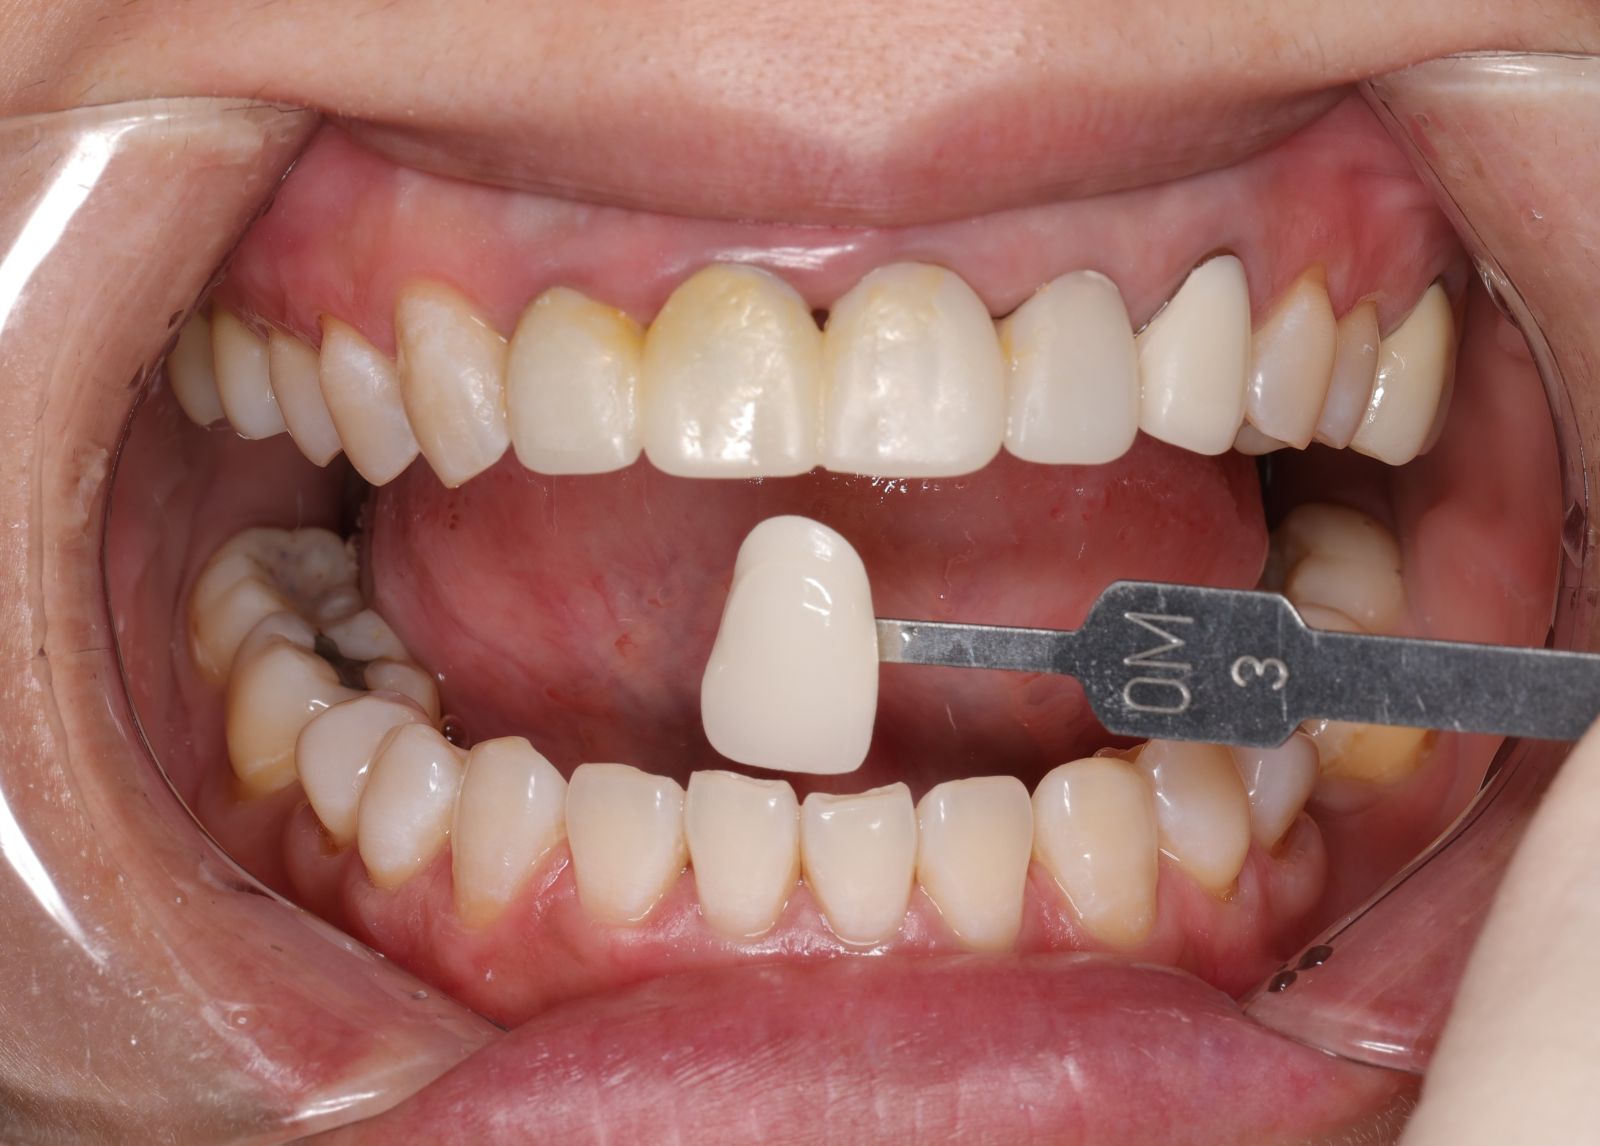

- 先把舊的假牙拆除後換成臨時假牙,期間先做冷光美白讓牙齒的基礎顏色變白,用保養型冷光美白,讓其他自然牙的部分可以白2~3個色階。一段時間讓顏色穩定後就可以當作正式全瓷冠的顏色參考。

經過數位微笑曲線設計,選擇自己喜歡的色階後就可以製作適合自己的美學全瓷牙囉!全瓷冠經過特殊處理呈現的通透感,讓牙齒白而自然透亮。